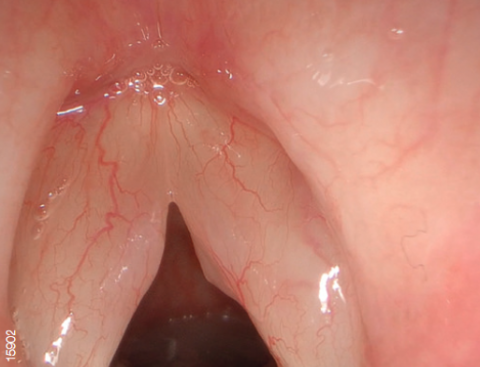

NBI - это оптическая технология, которая позволяет визуализировать мельчайшие структуры кровеносных сосудов и слизистой оболочки. В основе технологии лежит принцип поглощения гемоглобином волн определенного спектра (415 и 540 нм). Благодаря уникальным правилам распределения цветов, конечное изображение имеет цветопередачу отличную от обычной.

Свет, попадая в биологическую ткань рассеивается, часть волн (синих и зеленых) поглощается гемоглобином, остальное же распределяется в другие ткани. Поэтому цвет слизистой оболочки желудочно-кишечного тракта в основном определяется гемоглобином. Как упоминалось выше, NBI использует узкополосное освещение с центральной длиной волны 415 и 540 нм. Эти длины волн соответствуют двум пикам поглощения гемоглобина.

Данная технология позволяет с большей точностью визуализировать кровеносные сосуды и слизистую оболочку, а также диагностировать патологические процессы.